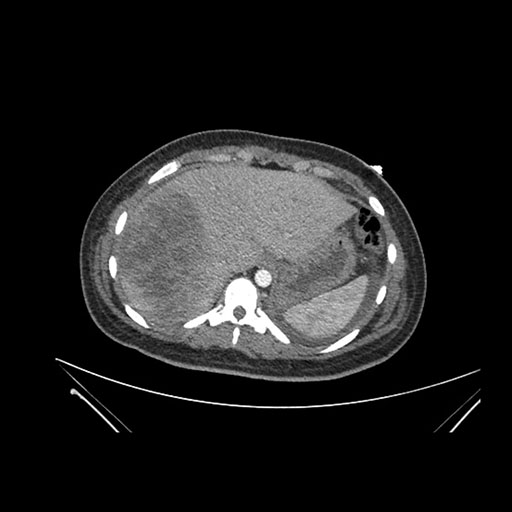

Imaging Analysis

Look through the patient's CT scan to identify any areas of concern for the necessary procedure.

Axial Venous

Based on initial findings, which issue(s) would you be most concerned about?